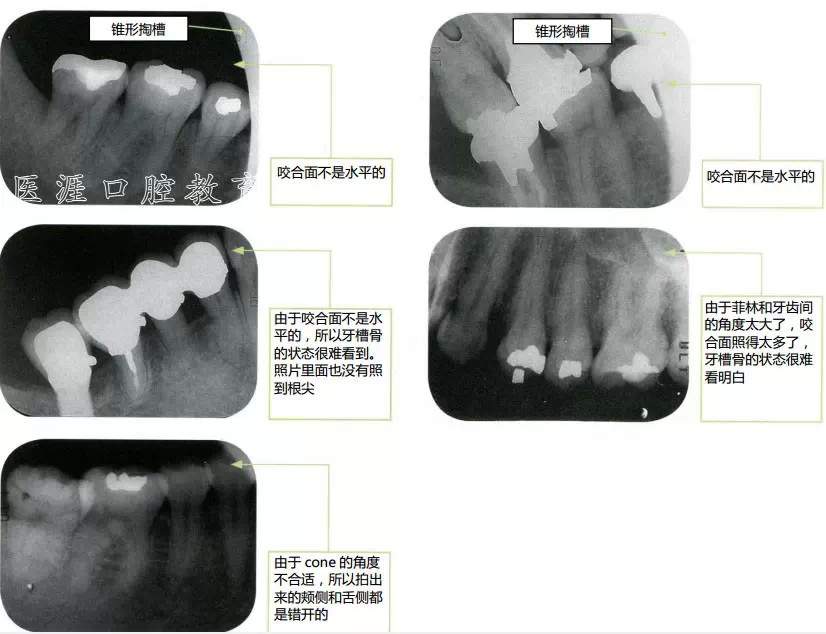

什么是不好的X光片1(14張法)

什么是不好的X光片2

cone的位置與想要拍攝的牙齒的位置錯開了